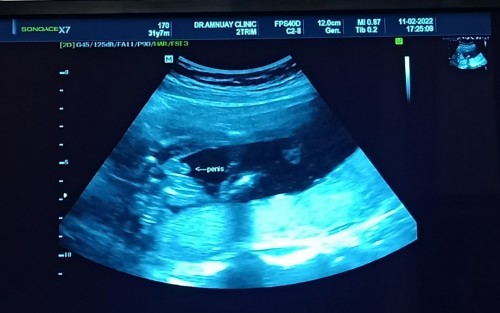

โชว์ไป1กรุบจ้า55 สมใจพ่อเขาเลย ลูกชาย🥰 #19W4